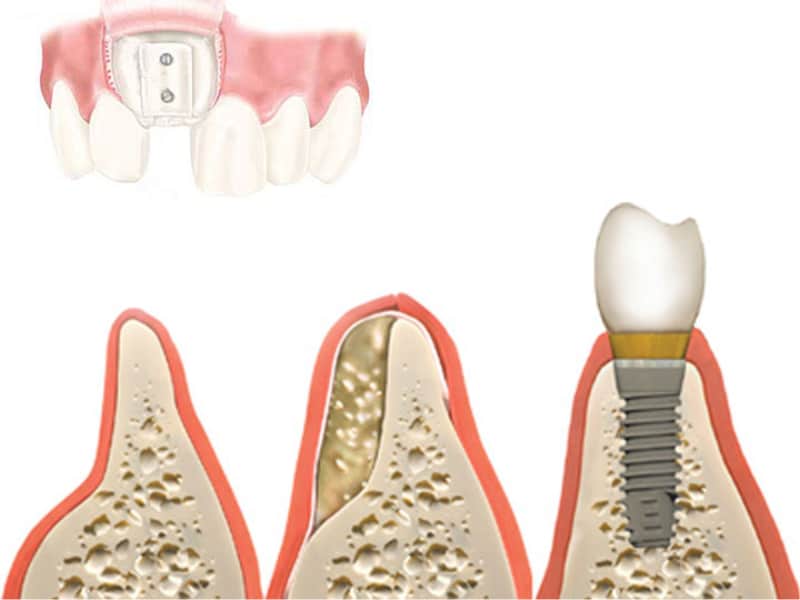

Implantologija

Dentalna implantologija je grana dentalne medicine koja objedinjuje znanje iz kirurgije, parodontologije i protetike. Marković Dental Clinic koristi najstariji, najistraživaniji i najkvalitetniji sustav dentalnih implantata Švedskog proizvođača Nobel Biocare.

Allon4 i Allon6 mostovi na 4-6 implantata

Patentirana metoda Allon 4 i Allon 6 predstavljena je još krajem 90-ih godina od strane Švedskog implantološkog sutstava Nobel Biocare. Kod većih resorpcija kosti gornje i donje čeljusti u 85% slučajeva moguće je ugraditi 4-6 implantata na točno određenim pozicijama i po određenim kutem.

Regeneracija kosti i mekog tkiva

Gingivalne recesije u narodu poznatije kao „povlačenje zubnog mesa” moguće je korigirati kirurškim zahvatom te vratiti gingivu (zubno meso) u fiziološki položaj mikrokirurškim tehnikama. Zahvati koje odrađujemo kod regeneracije kosti i mekog tkiva su podizanje dna sinusa (sinus lift) i nadomještanje izgubljenog volumena kosti (augmentacija kosti, regeneracija kosti).